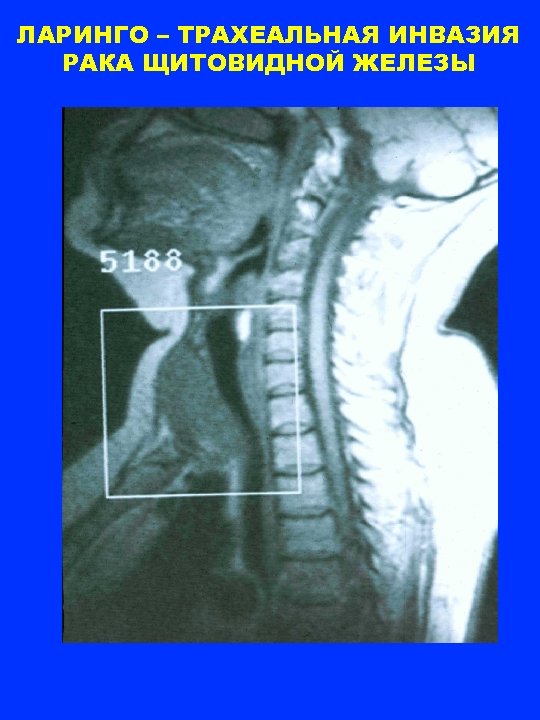

ЛАРИНГО-ТРАХЕАЛЬНАЯ ИНВАЗИЯ 33. 1% 17. 0% 9. 9% 4 - 20 21 - 40 41 - 60 61 - 84 возраст

ЛАРИНГО – ТРАХЕАЛЬНАЯ ИНВАЗИЯ РАКА ЩИТОВИДНОЙ ЖЕЛЕЗЫ